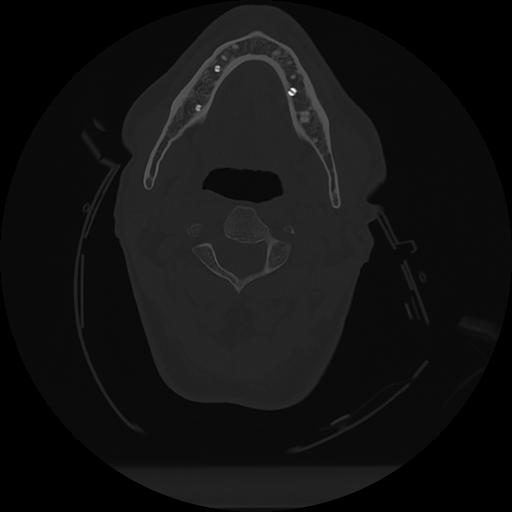

11 HUESO,,Axial,2.0,HUESO,,